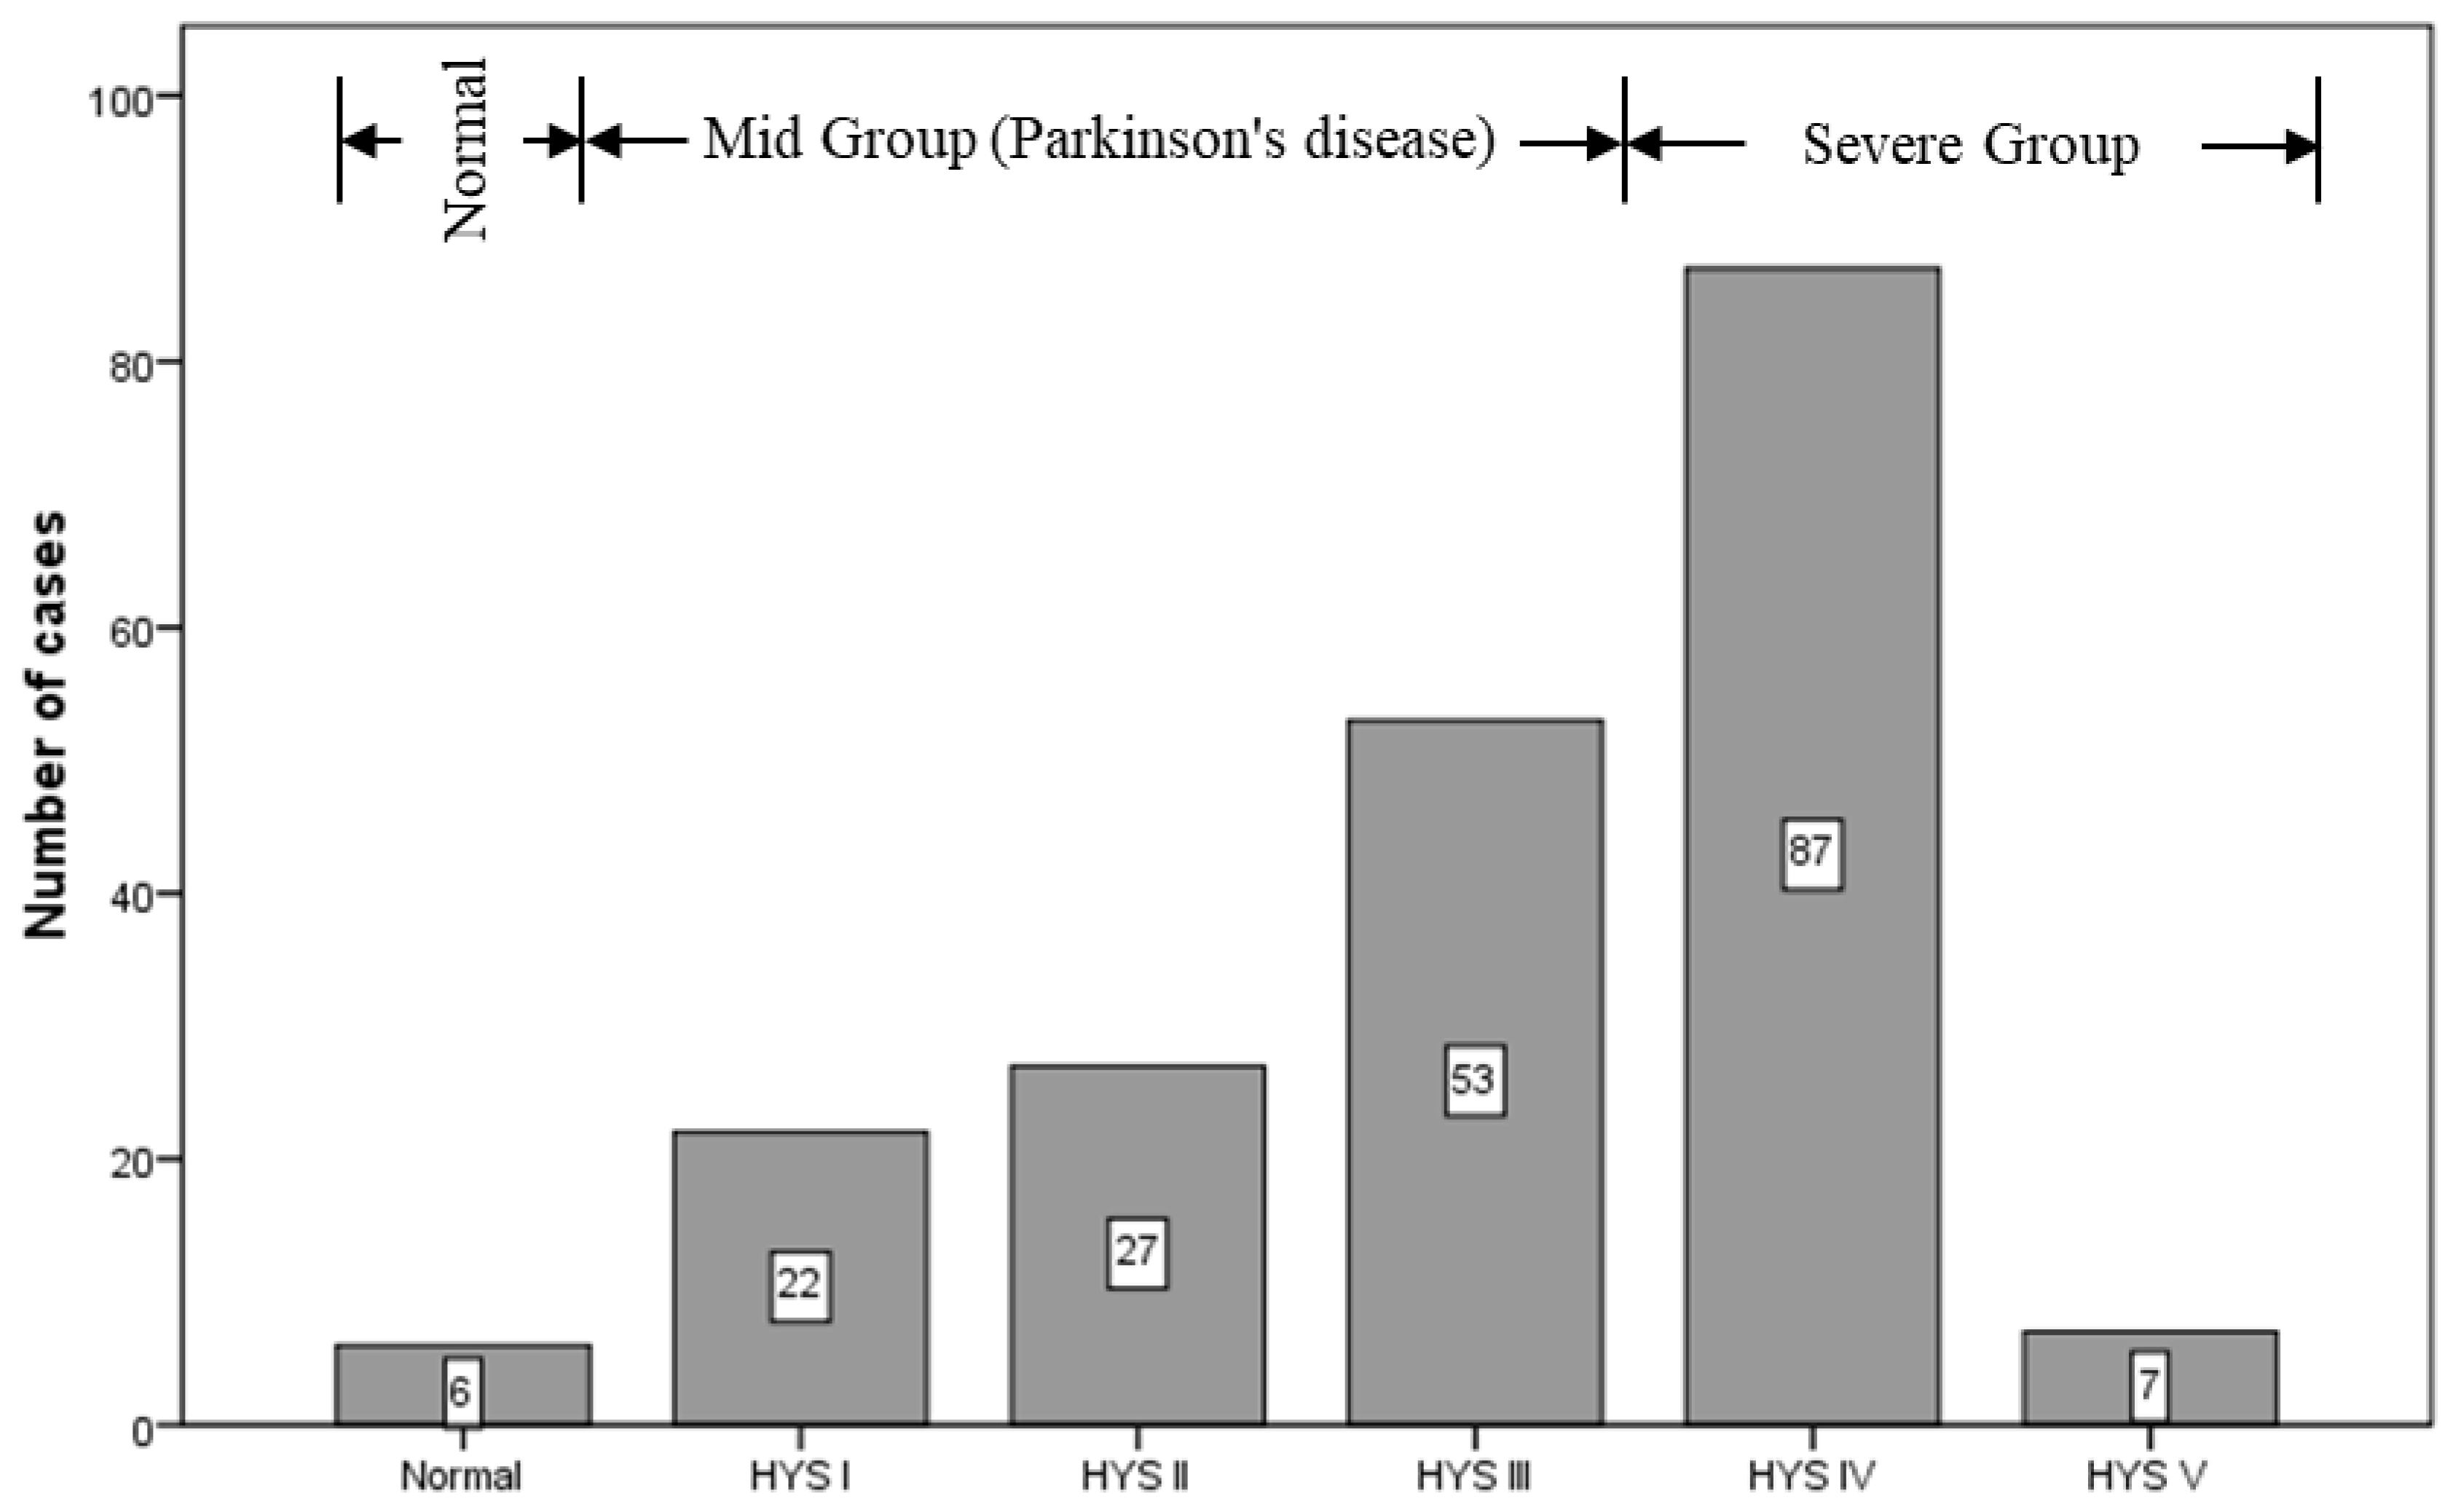

2.1. Subjects